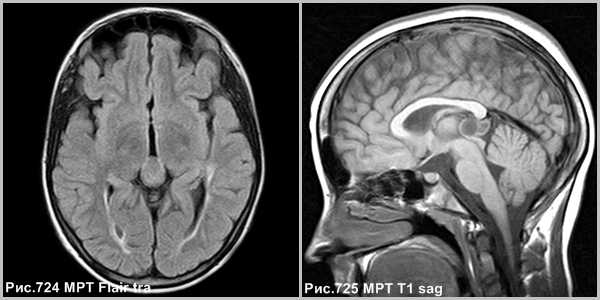

Пинеоцитома - доброкачественная опухоль, возникающая из ткани шишковидной железы, имеющая четкие контуры (рис.724, 725).

Пинеоцитома - доброкачественная опухоль, происходящая из паренхимы corpus pineale, хорошо ограниченное, инкапсулированное, медленно растущее, неинвазивное поражение. Опухоль может содержать кальцинаты по периферии [137]. Размеры образования могут быть различны, но это не связано с атипией опухоли. На КТ пинеоцитомы были описаны как → или слегка ↑, на МРТ это солидная фракция описывается, как ↓T1 и →Т2 [137].

Объёмное образование шишковидной железы, представленное мягкотканным образованием с наличием капсулы (стрелки на рис.729, 730). Пинеоцитома может иметь кисты (головка стрелки на рис.728).